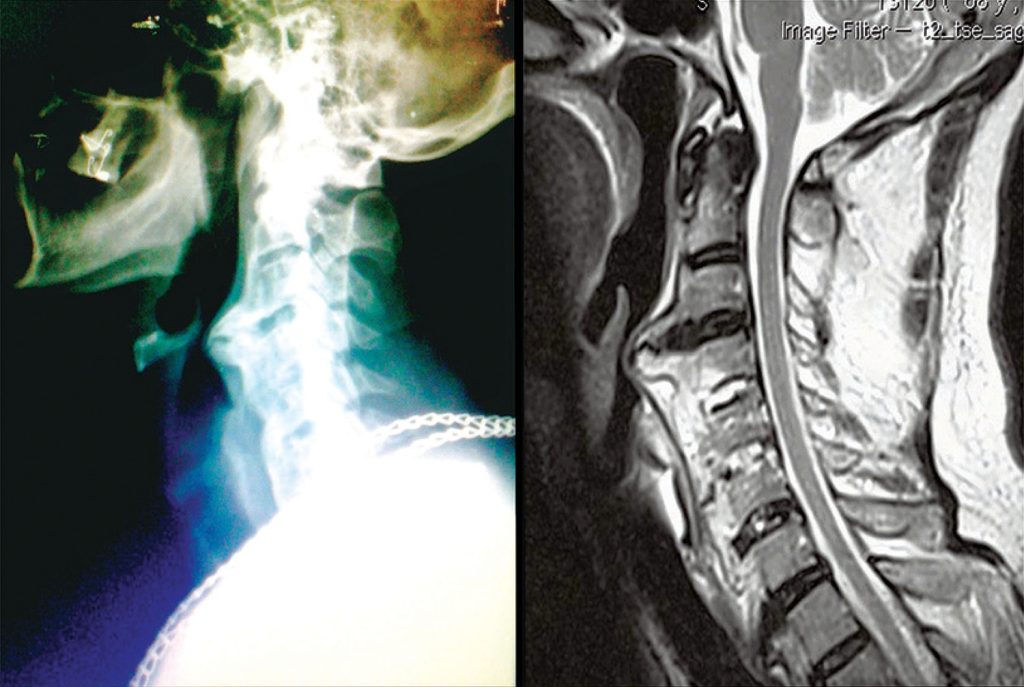

Lateral cervical X-ray and T2-weighted sagittal magnetic resonance. We observed an extensive calcification in front of vertebral bodies of C2 to C6 in topography of anterior longitudinal ligament. Esophagus and airways present a posterior compromising, which determine a stenosed segment that difficult orotracheal intubation at time of surgical procedure